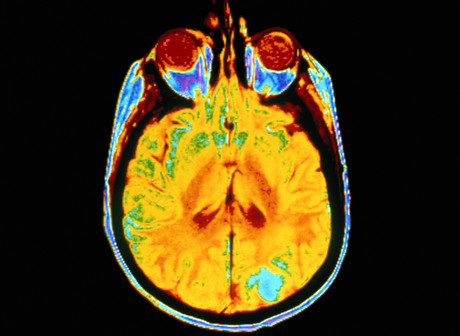

The researchers have used artificial intelligence to identify patterns of brain activity that make people less responsive to certain antidepressants. Their studies include findings from the 16-week EMBARC trial, intended to establish biology-based, objective strategies to remedy mood disorders and minimise the trial and error of prescribing treatments.

The two studies — which each included more than 300 participants — used imaging to examine brain activity in both a resting state and during the processing of emotions. Both studies divided the participants into a healthy control group and people with depression who either received antidepressants or placebo. Of the participants who received medication, researchers found correlations between how the brain is wired and whether a participant was likely to improve within two months of taking an antidepressant.

Dr Trivedi said imaging the brain’s activity in various states is important to get a more accurate picture of how depression manifests in a particular patient. For some people, he said, the more relevant data will come from their brains’ resting state, while in others the emotional processing will be a critical component and a better predictor for whether an antidepressant will work.

The Nature research used artificial intelligence to determine correlations between the effectiveness of an antidepressant and how a patient’s brain processes emotional conflict. Participants undergoing brain imaging were shown photographs in quick succession that offered sometimes conflicting messages such as an angry face with the word ‘happy’, or vice versa. Each participant was asked to read the word on the photograph before clicking to the next image.

However, rather than observe only neural regions believed to be relevant to predicting antidepressant benefits, scientists used machine learning to analyse activity in the entire brain. “Our hypotheses for where to look have not panned out, so we wanted to try something different,” Dr Trivedi explained.

AI identified specific brain regions — for example, in the lateral prefrontal cortices — that were most important in predicting whether participants would benefit from an SSRI. The results showed that participants who had abnormal neural responses during emotional conflict were less likely to improve within eight weeks of starting the medication.